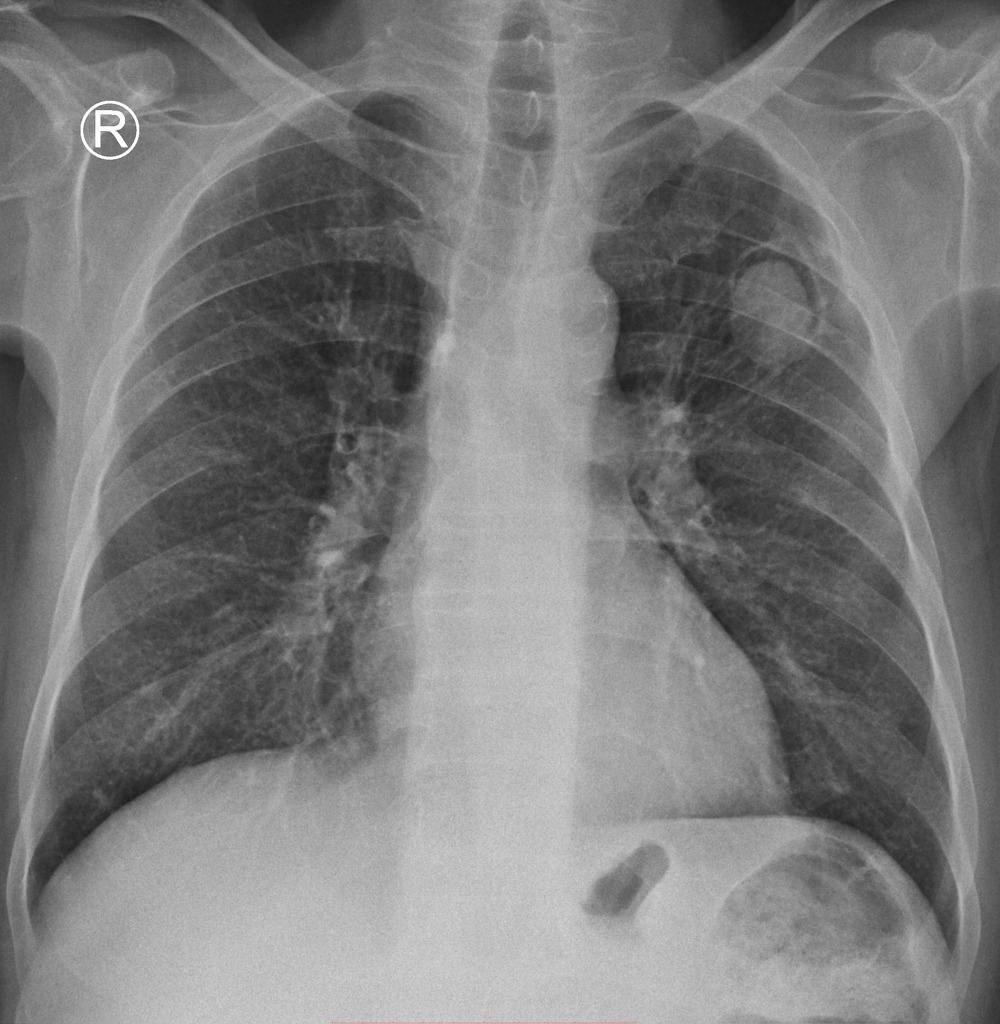

HOMEM DE 20 ANOS COM QUADRO DE INSUFICIENCIA RESPIRATÓRIA E HEMOPTISE. NEGA FEBRE

OPACIDADES DIFUSAMENTE DISTRIBUÍDAS, COM PADRÃO SUGESTIVO DE PREENCHIMENTO ALVEOLAR, PREDOMINANTE EM LOBO INFERIOR DIREITO

HEMORRAGIA ALVEOLAR